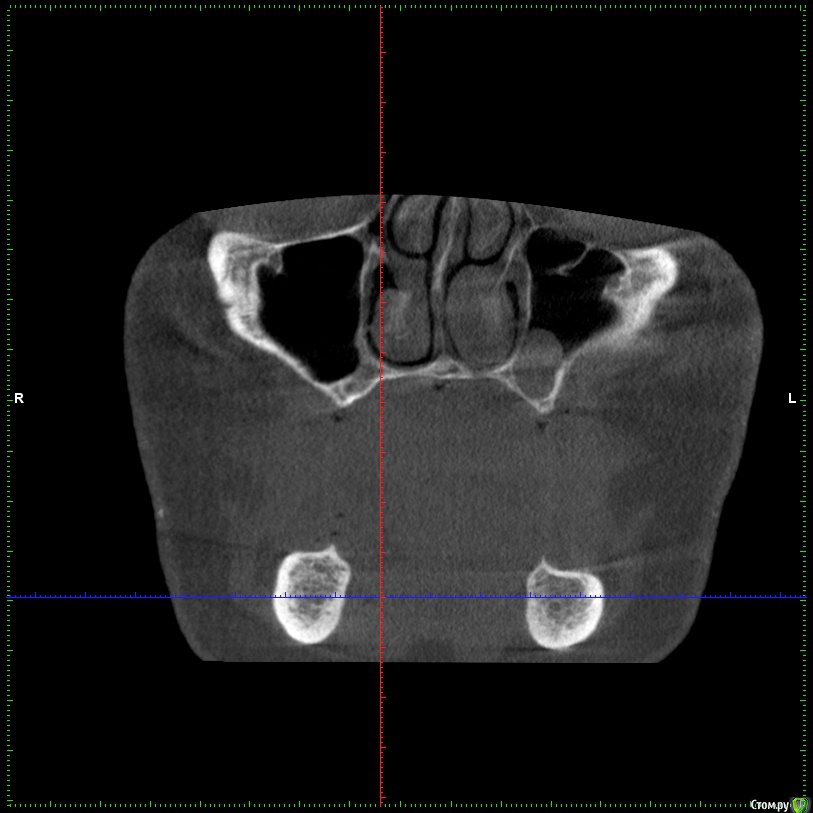

Aleksey_Mironov Опубликовано 11 января, 2018 Автор Поделиться Опубликовано 11 января, 2018 здравствуйте коллеги!! вот такой сюрприз..хочу сделать синус лифтинг.. что за образование можеть быть? Ссылка на комментарий

Борис80 Опубликовано 11 января, 2018 Поделиться Опубликовано 11 января, 2018 Не совсем уверен, тк недостаточно срезов видно, но я бы сказал насморк или что-либо подобное(это по поводу тени) и , что значительно неприятнее, это костная перегородка на дне пазухи Ссылка на комментарий

колесников Опубликовано 11 января, 2018 Поделиться Опубликовано 11 января, 2018 (изменено) Может образоваться перфорация мембраны. Делайте 2 окна Изменено 11 января, 2018 пользователем колесников Ссылка на комментарий